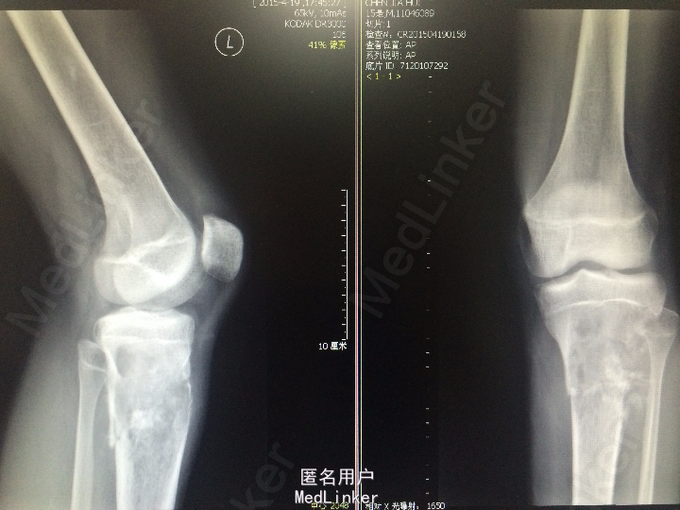

诊断:恶性骨肿瘤:骨肉瘤? 处理:完善相关检查,局麻下行左胫骨肿物穿刺活检术,病理诊断为骨肉瘤。遂进行AP方案诱导化疗,其中吡柔比星针(合)40mg d1-2+顺铂针 30mg d1-5,过程顺利。后患者肿瘤疼痛加重,予止痛治疗,住院期间下床时不慎扭伤左下肢后疼痛加重,行左膝关节X光检查提示病灶部位骨折,断段对位对线上课,暂予止痛、夹板固定,择期手术治疗。后行全麻下左大腿截肢术。术后予止痛、补液、预防感染等治疗,患者恢复良好。

一月后返院继续行辅助化疗。骨肉瘤是骨恶性肿瘤中最多见的一种,是从间质细胞系发展而来,下肢负重骨在外界因素(如病毒)的作用下,使细胞突变,可能与骨肉瘤形成有关。该患者年纪符合发病年龄段,目前来说骨肉瘤经病理确诊后,即可开始前期的化学或放射性治疗,切除肿瘤组织是骨肉瘤治疗中重要的步骤。肿瘤组织切除后的巩固性化学或放射性治疗对控制肿瘤转移,提高生存率非常重要。治疗骨肉瘤应行根治性手术。有条件者也可做局部广泛切除而保留肢体。但该患者由于出现病理性骨折,保全肢体可能性较小,故采用截肢手术加辅助化疗的治疗方法。